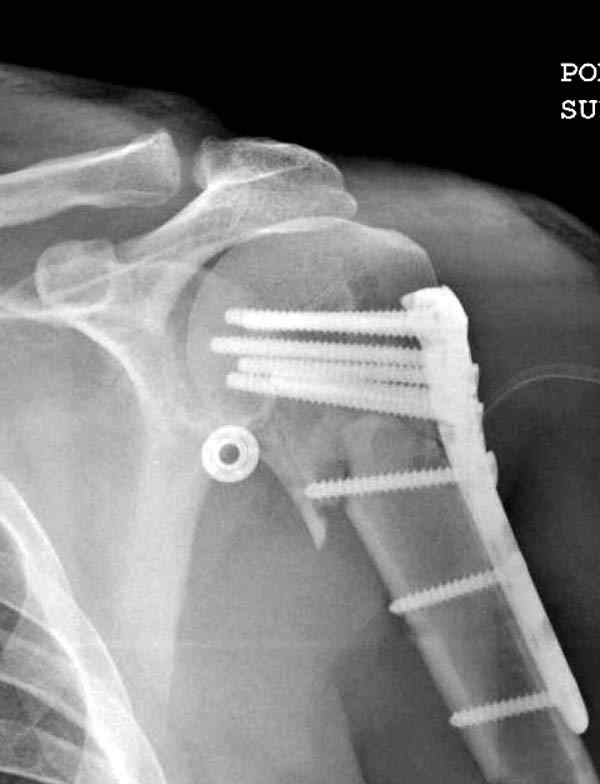

Здесь пример открытой репозиции 57 летнего с переломом плеча (1,2)  смещение обнаружено на  интероперационном снимке. При нормальной прямой проекция (3) угловое смещение обнаружили в аксиальной проекции (4)

После устранения смещения пластина установлена выше (5,6,7) и финальные снимки (8,9,10)